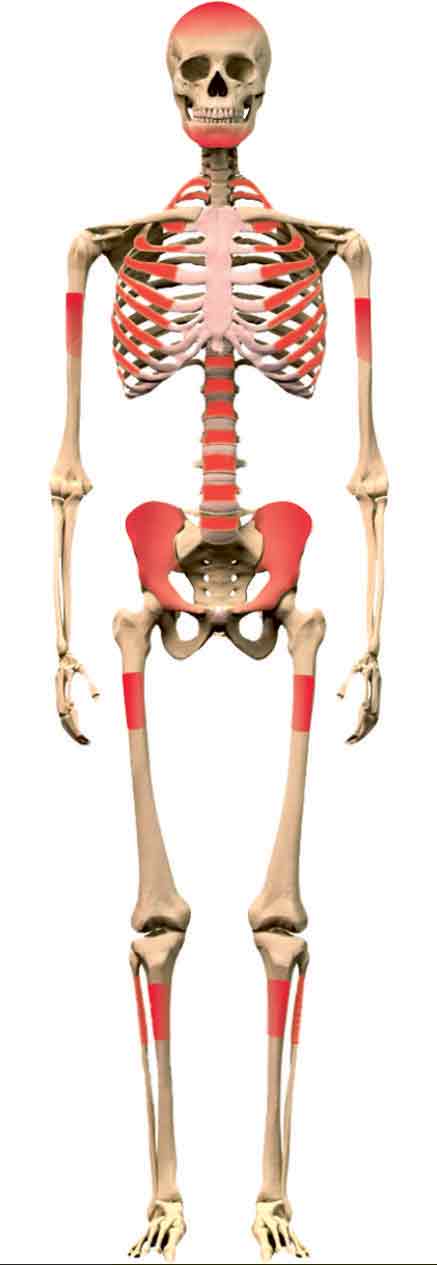

![]() توزع الورم ذي الخلايا العرطلة (رسم طرف واحد). | |

وجود الورم في الظنبوب. | |

توزع داء إوينغ. |